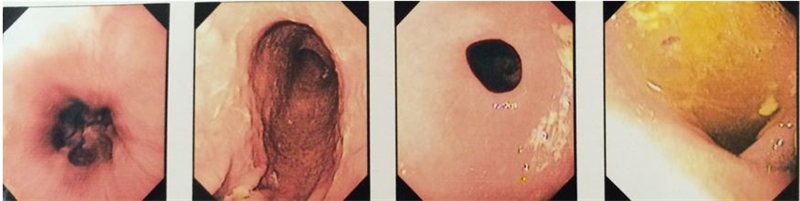

• Nội soi dạ dày tá tràng (hình 3)

Hình 3: Hình ảnh nội soi dạ dày tá tràng sau 10 ngày điều trị

Kết luận: Thực quản: bình thường; Dạ dày dịch trong, niêm mạc bình thường, nhu động mềm mại, không thấy ổ loét; Bờ cong lớn, bờ cong nhỏ không thấy xung huyết, không có ổ loét; Lỗ môn vị bình thường.